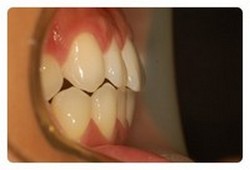

치아교정 전후 사진을 비교해보니 쏘옥 들어간 앞니 ~~~

보다 더 놀라운건 교합 !!

상하악이 거의 맞물리고 잇엇는데

지금은 윗니가 아랫니를 싸악 ~~~ 덮는 이쁜 모양새 ~~~